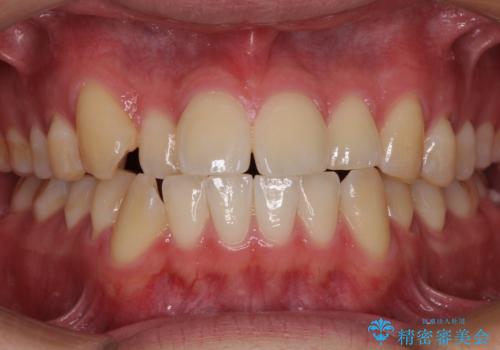

矯正歯科治療 → 叢生(でこぼこ・八重歯)

気になる八重歯を目立たない装置で改善 ハーフリンガル矯正